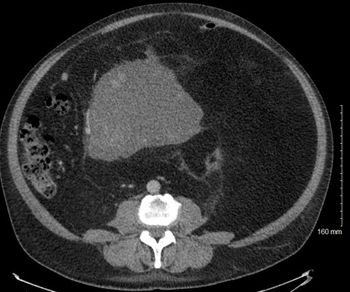

A 23-year-old young man presents with pain in his left calf. A physical examination detects a mass in the calf area. What is your diagnosis?

A 23-year-old young man presents with pain in his left calf. A physical examination detects a mass in the calf area.

Based on the image shown, what is your diagnosis?